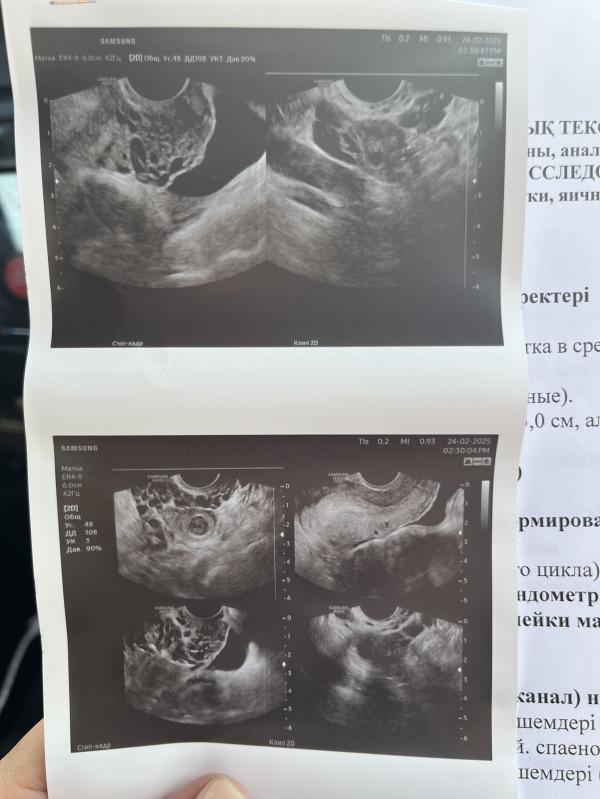

Хотела спросить это нормально?, завтра пойду на прием.Хочу забеременеть планирую точнее и вот думаю заключение нормальное ли.Сказали воспаление есть и варикоз малого таза кажется

Вот тоже хочу забеременеть но не могла пошла на узи вот такие дела теперь думаю может после лечение забеременею

Не нормально, трубы у Вас с двух сторон написано воспалены. Вот это влияет на беременность. Они непроходимые из-за этого могут быть. ВРВ думаю не так влияет как вот андексид. У Вас боли должны быть.